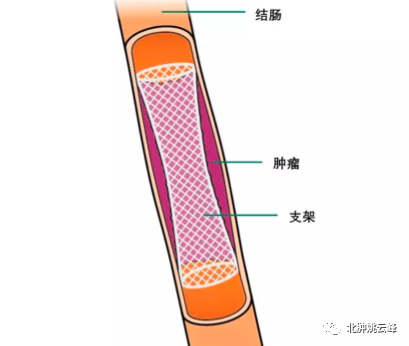

“内放疗”是一种放射性粒子植入术。医生利用现代影像学技术将具有放射性核素的粒子直接插植到肿瘤病灶内或肿瘤周围,放射性粒子通过持续释放射线对肿瘤细胞进行杀伤。“内放疗”属于高度适形放疗的一种,目前国内所应用的放射性粒子主要指碘125粒子。8Wz帝国网站管理系统

我“身高”4.5mm,“腰围”0.8 mm,肚子里装着吸附碘125粒子的银棒,外壳为0.05 mm厚的钛金属。我是“0-0-7”哦,可以24小时持续工作(释放能量)。另外我射线射程短(组织间有效射程直径只有1.7cm),大部分射线能量均被瘤体及组织所吸收,所以大家不用害怕我,无须特殊防护。